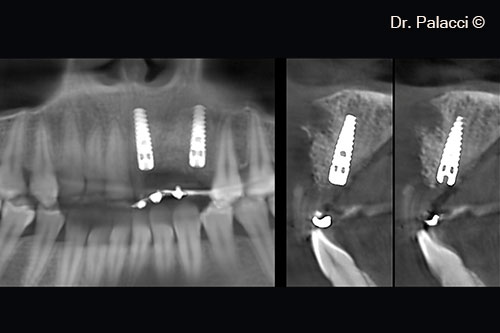

Hai trụ cấy ghép NP 3.5mm đã được đặt và ổn định tốt (giá trị ostell trên 70)

Một lớp GTO bổ sung được đặt ở vị trí môi

Một lớp bổ sung được đặt ở vị trí yên ngựa để tăng chiều cao theo phương thẳng đứng